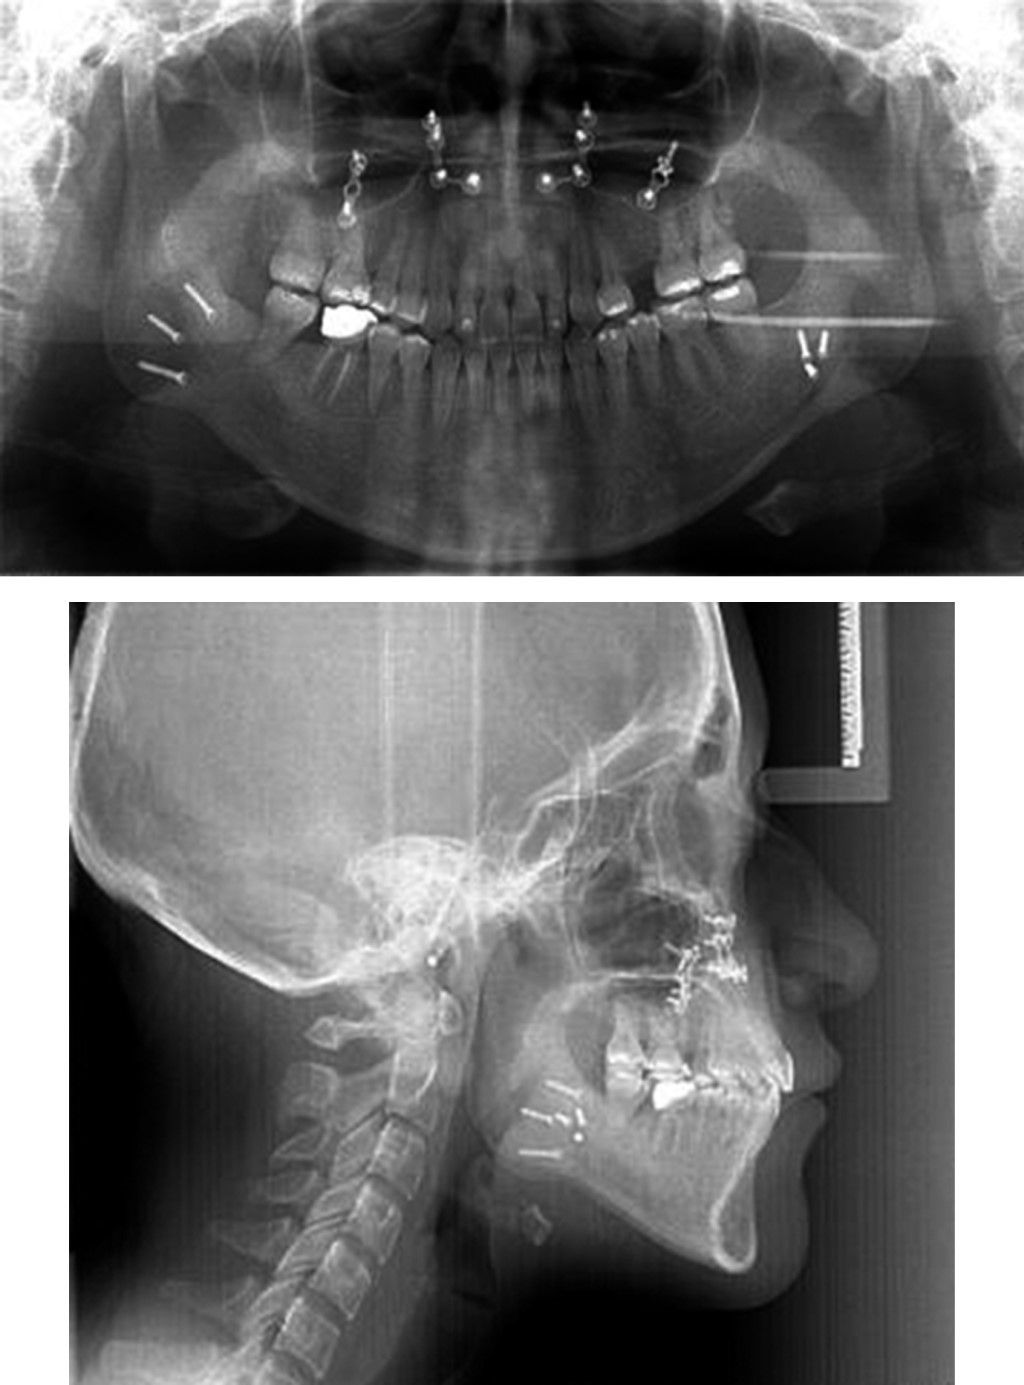

Presurgical 0.019" × 0.025" stainless steel surgical arches with crimpable hooks were placed. The surgical procedure consisted of bilateral branch sagittal for correction of laterognathia, mandibular retroposition, and maxillary impaction for correction of vertical excess. Eight 8 mm fixation screws were used, three on each side. Seven days after surgery, intermaxillary elastics were placed to achieve adequate seating and prevent the muscle force from generating undesirable movements. These elastics had a class II vector (Figure 9).

Orthopantomography was taken to verify radicular parallelism, and control of the osteosynthesis material (Figure 10). The patient continued using elastics to correct muscular patterns of occlusal settlement. Consultation was made with the Department of Periodontics, DEPeI, UNAM, for the future placement of dental implants, where they told us to have an adequate space of 7 mm for the upper left premolar (Figure 11).

Figure 9

Figure 10

Figure 11